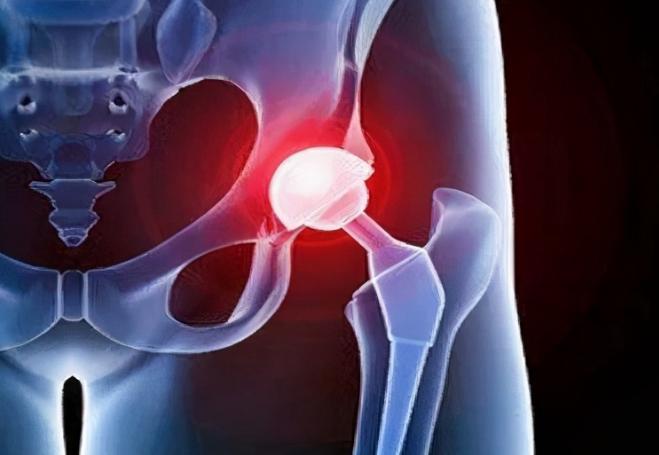

髋关节疼痛还有可能是外伤所导致的,比如出现过比较严重的骨折或者是骨盆骨折等问题,都有可能导致胯关节疼痛。 在出现外伤的情况下,还有可能导致髋关节变形或者是活动受到很大的限制。 当然也有一部分人是因为长时间错误的姿势导致髋关节出现疼痛。

除了上面这些原因引起髋关节疼痛之外,导致这一部位出现疼痛的原因,还有可能和受凉以及过度疲劳等因素有关。 不管是什么原因引起的疼痛,都必须要到医院进行及时的医治。

这样才能大大缓解疼痛给身体带来的不适感。 在治疗髋关节疼痛的同时,还需要改善不良的生活习惯,避免长时间久坐或者是经常熬夜。